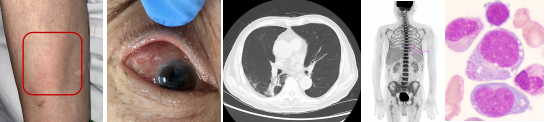

在2020年12月,Beck[1]等人发现了一种与UBA1基因突变相关的自身炎症性疾病,被命名为VEXAS(空泡、E1酶、X-连锁、自身炎症、体细胞)综合征。这是一种严重的进行性疾病,通常在中老年期发病,常伴有发热,并可能累及皮肤、软骨、肺、血管等多个器官,合并血液系统疾病如巨幼细胞贫血、血小板减少症、静脉血栓、血液系统恶性肿瘤等(见下图)。临床上,VEXAS 综合征表现复杂,容易被误诊或误治。

VEXAS 综合征的临床表现(图源:如图示)